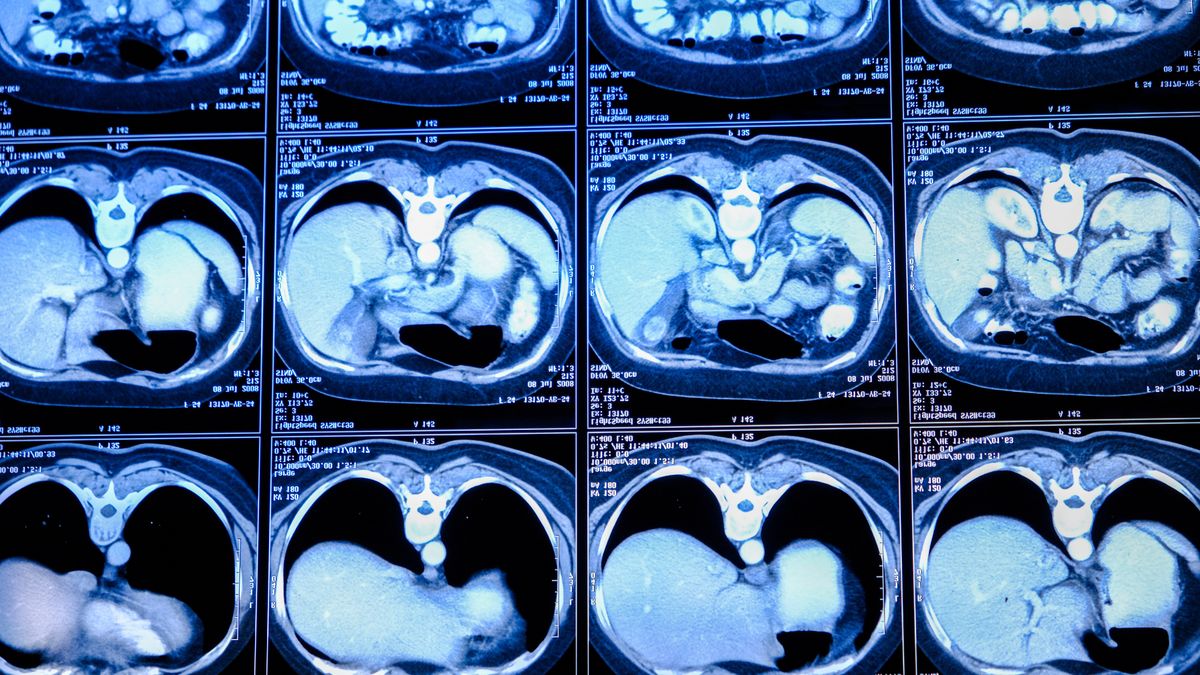

Když jsem potratila, mohla jsem absolvovat odkládanou magnetickou rezonanci, jejíž výsledky vedly k lumbální punkci a potvrzení roztroušené sklerózy. Co se ale dělo mezi rezonancí a lumbálkou nikdo nevěděl. Prožívala jsem tehdy po psychické stránce nejhorší období v životě.

Poslední pokus v 11:01 (tudíž minutu po konzultačních hodinách) byl úspěšný. Sestra mě přepojila na doktorku. V ten moment kolem mě projíždělo asi deset kamionů a já slyšela jen dvě třetiny informací. Zachytila jsem slova jako nález, drobné tečky na snímku, zjizvení po viróze, myelinová pochva, nervová vlákna, lumbální punkce.

Zjevily se mi články o roztroušené skleróze. Příznaky až děsivě odpovídaly tomu, co jsem řešila. Čím víc jsem se do tématu nořila, tím mi to bylo jasnější: mám roztroušenou sklerózu. Úzkost narůstala a dosáhla obřích rozměrů, když jsem se začetla do příběhů lidí s touto nemocí. Pán na vozíku, co ovládá počítač tužkou v puse. Žena, která kvůli nemoci musela přerušit těhotenství.